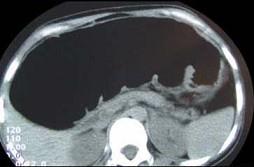

女,30岁,便秘、腹痛腹胀多年,CT检查如图,最可能的诊断是 ( )A.结肠肠梗阻B.先天性巨结肠C.结肠肠套叠D.结肠肠扭转...

问题 女,30岁,便秘、腹痛腹胀多年,CT检查如图,最可能的诊断是 ( )

选项 A.结肠肠梗阻 B.先天性巨结肠 C.结肠肠套叠 D.结肠肠扭转 E.结肠肠栓塞

答案 B